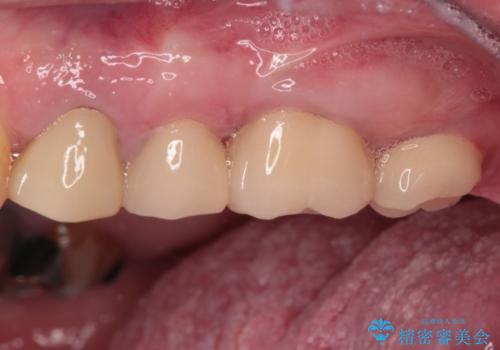

下顎大臼歯の抜歯決断までに時間がかかったため、治療期間はやや長くなりましたが、安定した咬み合わせとなり、痛みもなく安心して噛めるようになりました。